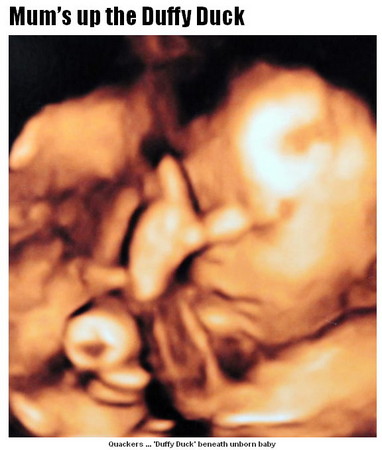

▼「我已經蝸居7個月了,好無聊啊!」(圖/設計對白,取自英國《太陽報》)

英國24歲的年輕準媽媽斯艾瑞卡(Erica Swindlehurst),日前到醫院為28周大的胎兒做3D立體超音波掃描,忍不住大笑──胎兒的懷抱彷彿有一隻黃色塑膠鴨(見上圖左下角)!她在受訪時說,「看來貝比已經有玩具了。」當然她也知道,這只是照片上陰影造成的錯覺。